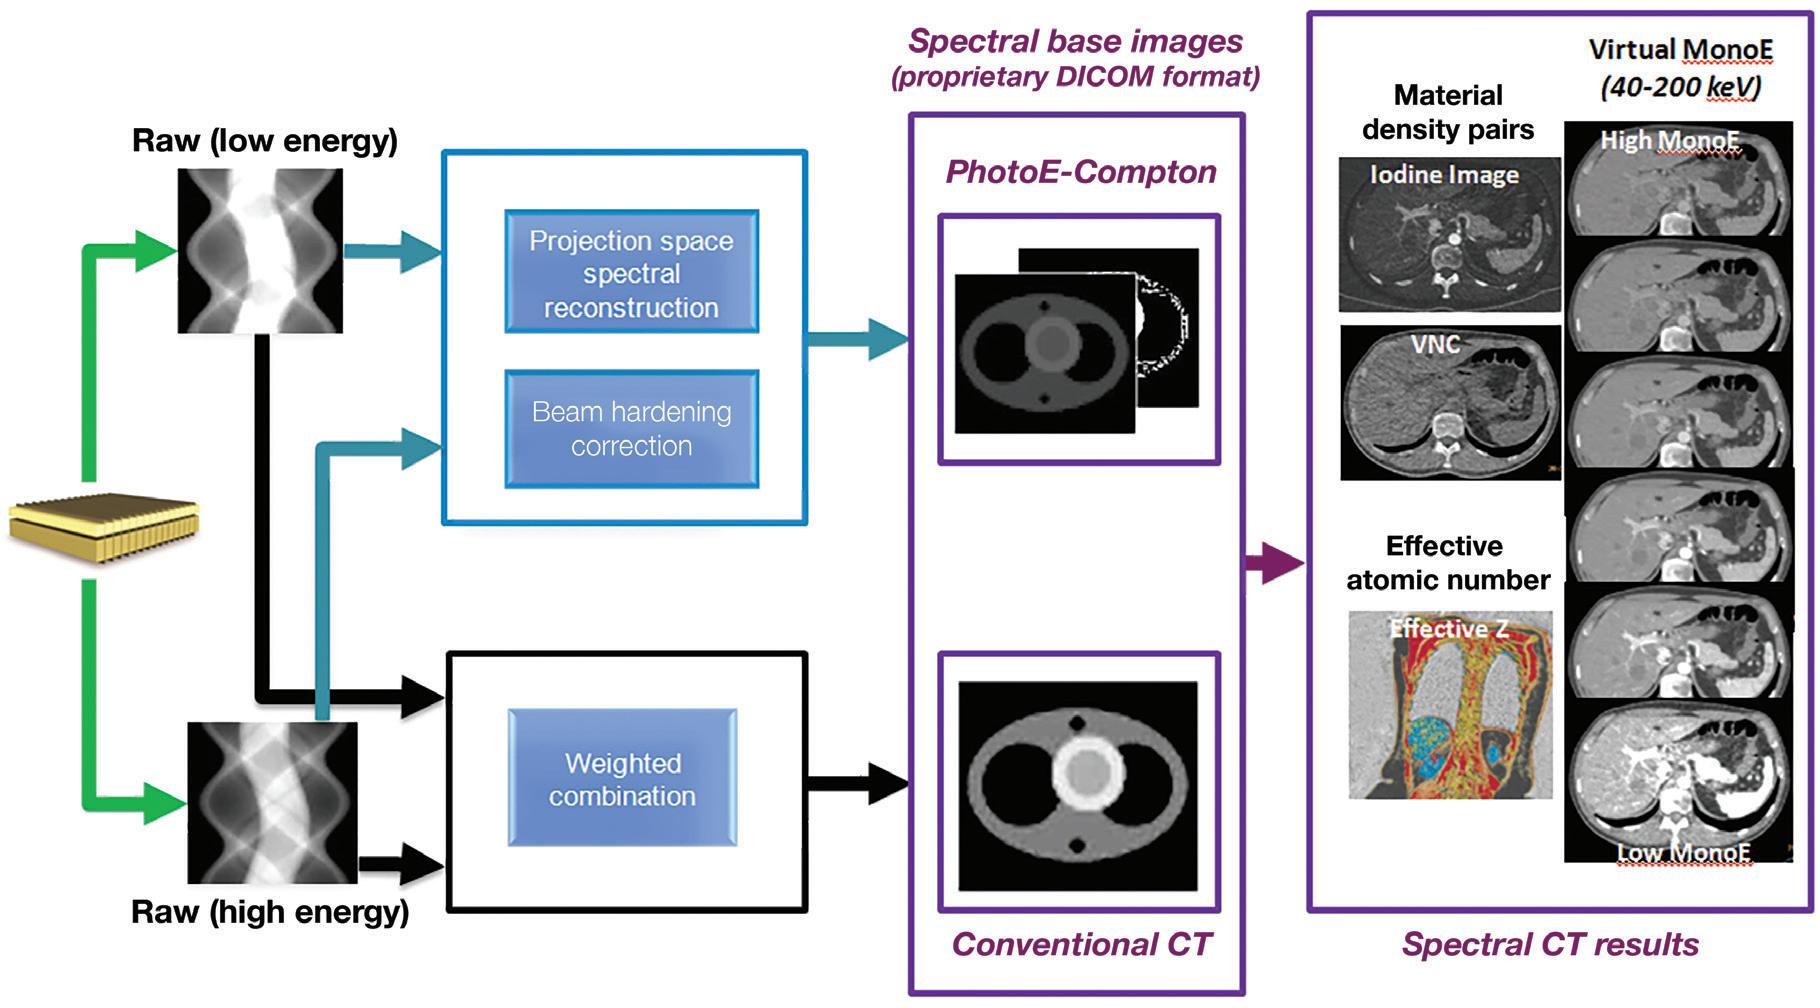

In practice, a single CT scan is performed (e.g., 120 kVp or 140 kVp), and the first layer (upper) encountered by the X-ray photons absorbs most of the low-energy photons, while the bottom detector layer absorbs the remaining higher energy photons (Figure 1). In contrast to other approaches of dual-energy CT, there is no need to redundantly expose materials with both low and high kVp. Furthermore, since the spectral energy separation is intrinsic to the detection system, rather than sequentially generated at the X-ray source, this approach eliminates the time lag of sequential techniques, making it ideal for imaging moving organs, as in cardiac CT. In other words, the dual-layer technique is fully registered both spatially and temporally, and it has no spatial shift or dead time such as in dual kVp or dual tube techniques. The low- and high-energy projection data are perfectly aligned, enabling projection-based spectral decomposition, and providing the opportunity to properly account for beam hardening effects without the need for spatial or temporal interpolations.6,7

The low- and high-energy measured attenuations can also be combined to provide the attenuation over the entire X-ray spectrum and used to reconstruct a “true” conventional CT image (Figure 1), without the need to compensate for warping and shifting due to the time lags. This is different from the other currently available dual-energy technologies where low- and high-kVp images are obtained and blended to obtain a surrogate “conventional” image data set. The use of a single source also obviates the cross-scatter limitation of dual-source techniques 8 and enables full 50 cm field of view (FOV) imaging.

A schematic illustration of the dual-layer detection system. The upper layer is made of a low density scintillator (yttrium-based) which is almost transparent to high X-ray energies, while the lower layer is made of a traditional GOS (gadolinium oxysulfide) scintillator which can absorb up to 99% of those high energies. The acquisition enables the decomposition of the measured attenuation into the Compton-Scatter-like and photoelectric-like absorption basis. The low- and high-energy measured signals are also combined to provide the signal resulting from the entire X-ray spectrum which is used to reconstruct a “true” conventional CT image. From the spectral base images (SBI), all spectral results can be regenerated at the IntelliSpace Portal (ISP) console. An SBI follows the DICOM standard, and can be stored on the PACS of the hospital and retrieved at the ISP (Philips IntelliSpace Portal) console in the case a spectral retrospective analysis is needed.

IQon Spectral CT users may plan the reconstruction of any spectral result prospectively in the exam card describing the acquisition/reconstruction parameters of a particular scan protocol. Spectral base images (SBI) can also be reconstructed, which contain the conventional CT together with the basis images, Compton-like (αc(x,y,z)) and photoelectric-like (αp(x,y,z)) images (see Figure 1). From an SBI, all spectral results can be regenerated at the IntelliSpace Portal (ISP) or scanner console. An SBI follows the DICOM standard, and can be stored on the PACS of the hospital and retrieved at the ISP (Philips IntelliSpace Portal) console in the case a spectral retrospective analysis is needed. As an alternative, a light “Spectral Viewer” version, the Magic Glass on PACS (MGoP), can also be installed on the PACS viewing stations. This light spectral viewer enables the regeneration of all the required spectral results in the PACS viewing environment. IQon Spectral CT systems provide a variety of images or spectral results as listed below: